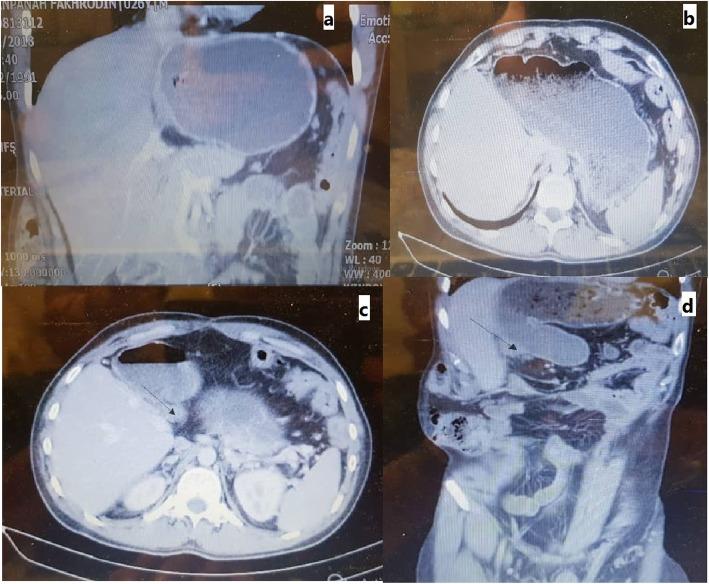

A 24-year-old male referred with chief complaints of abdominal pain, nausea, and vomiting from 1 month prior to admission. Computed tomography showed a large liver mass in the left lobe of the liver with involvement of retrohepatic inferior vena cava (IVC), in favor of hepatocellular carcinoma. After hepatectomy, the common bile duct was completely removed. A 4-cm Dacron graft was anastomosed to the inferior and top of the IVC. A temporary portocaval shunt was placed, and ex situ resection of the left lobe of the liver was done. Remnant of the liver was implanted. Reconstruction of the bile duct was done using a Roux-en-Y technique, and autotransplantation of the liver was then completed. During a 4-year follow-up, the patient had no complaints and is in good conditions.

一名 24 岁男性因腹痛、恶心和呕吐就诊,症状从入院前 1 个月开始出现。计算机断层扫描显示左肝叶有一个大的肝肿块,伴有肝后下腔静脉(IVC)受累,考虑为肝细胞癌。肝切除术后,胆总管被完全切除。将 4 厘米的涤纶移植物吻合到 IVC 的下侧和顶部。放置临时门腔静脉分流术,并进行离体左肝叶切除术。剩余的肝脏被植入。使用 Roux-en-Y 技术进行胆管重建,然后完成肝脏自体移植。在 4 年的随访中,患者无任何不适,状况良好。